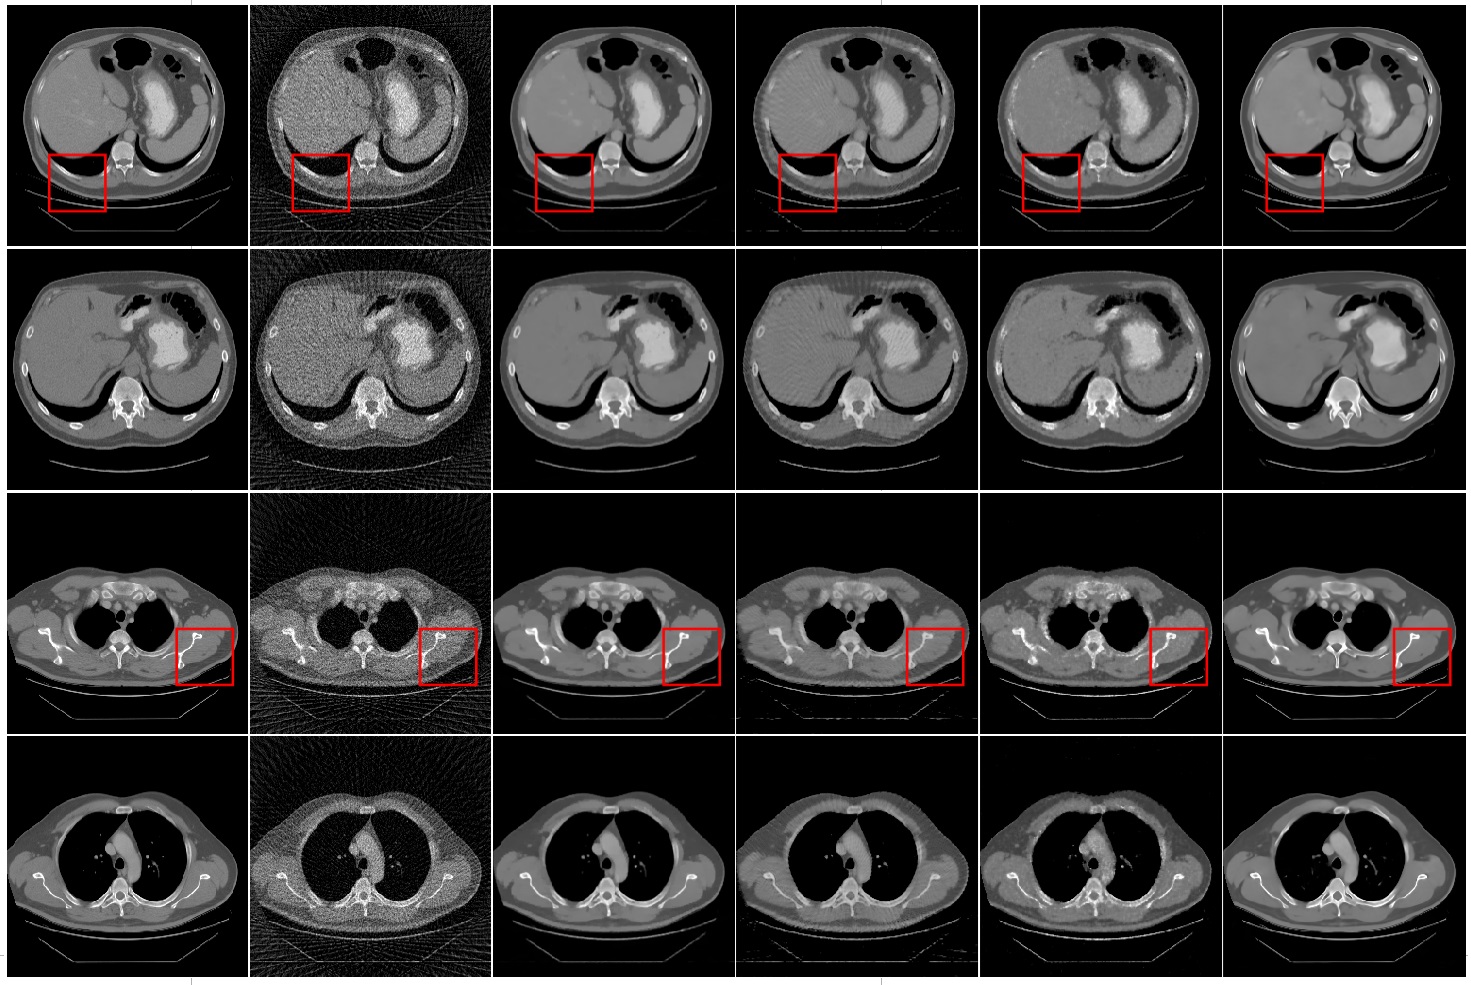

Fig. 9 lists some example images which are reconstructed from 60 views with FBP, TV based method, FBP+U-net, Recon-NN and the FAR-net, respectively. It is obviously that images reconstructed from FBP suffer with heavy artifacts caused by under-sampling projection. The quality of reconstructed image is degraded by streak artifacts distributed across the whole image. All these methods suppressed image artifacts and improve image quality to various levels.The TV based method and FAR-net take more efficiently for suppressing the streak artifacts and achieving better performance in image quality. However, as shown in the Fig. 9 (c), TV based method suffered from a blocky effect and also smoothened some important small structures, such as image edge.

The example results of FBP+U-net method are shown in Fig. 9 (d). It is demonstrated that FBP+U-net removes major artifacts but some smaller streak artifacts are still available.The results of FAR-net are shown in the last column of Fig. 9. It is illustrated that the reconstruction image has no obvious blocky effect and has a best performance than other methods in low contrast region.

Fig.10 shows the zoomed in region of interest (ROI) marked by in Fig. 9. As indicated by the red arrows and circles, it is noticed that the FBP, TV based and FBP+U-net make the edges and low contrast region blurred or distorted, where FAR-net method can still maintain the structure.